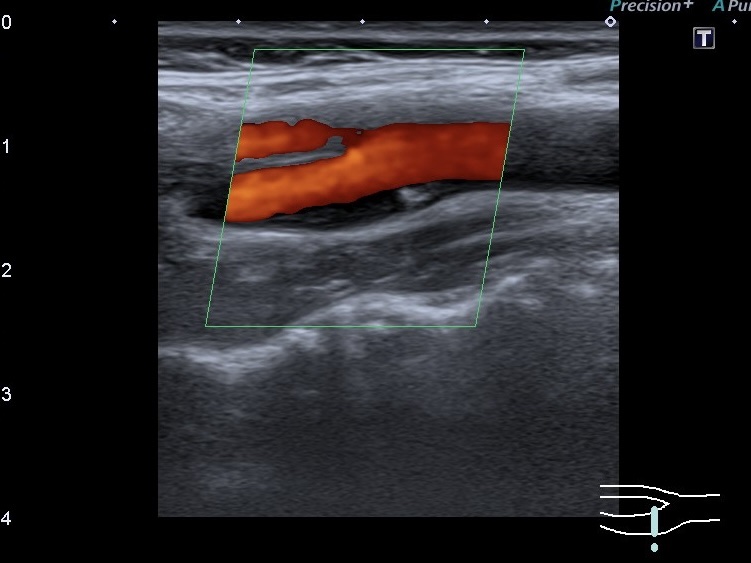

Последнее время при проведении УЗИ сосудов шеи большее внимание уделяется тому чтобы оценить типы атеросклеротических бляшек(АСБ). В зависимости от типа бляшки можно сказать о степени риска возникновения инсульта у пациента. Существует несколько классификаций АСБ. Одна из них Plaque-RADS делит бляшки на 4 категории. Самая опасная АСБ по этой классификации это 4 категория, куда входят бляшки, осложнённые внутренними кровоизлияниями, тромбозами, с повреждённой фиброзной покрышкой. К умеренному риску относятся АСБ 3 типа, которые также делятся на 3 подтипа (а, b, c). К 3а типу относятся АСБ с толстой фиброзной покрышкой, к 3б типу- с тонкой покрышкой. Это при условии, что эту покрышку есть возможность оценить. А вот уже к 3с типу относятся бляшки с изъязвлениями (прерывистой покрышкой)

Разница между 2 и 3 категориями в толщине стенки (максимальная толщина стенки, где бляшка до 3мм-2 тип или больше 3 мм- 3тип).2 категория АСБ считается с низким риском инсультов.

До данной классификации атеросклеротических бляшек существовала долго классификация нестабильности АСБ по эхогенности (Gray-Weale-Geroulakos). Учитывая, что названия классификаций атеросклеротических бляшек многим клиницистам мало известны, мы считаем важным описать характеристики АСБ по её стабильности в первую очередь. К примеру, нестабильная (гомогенная гипоэхогенная) АСБ или нестабильная (гетерогенная, преимущественно гипоэхогенная АСБ) с изъязвлением.